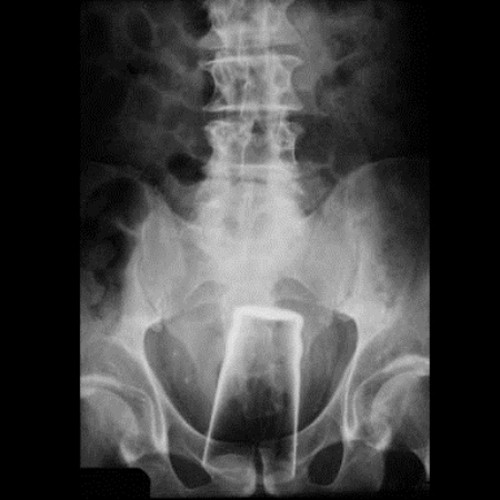

Thật khó hiểu vì sao chiếc ly thủy tinh này lại có cơ hội đi sâu vào vùng xương chậu của khổ chủ.